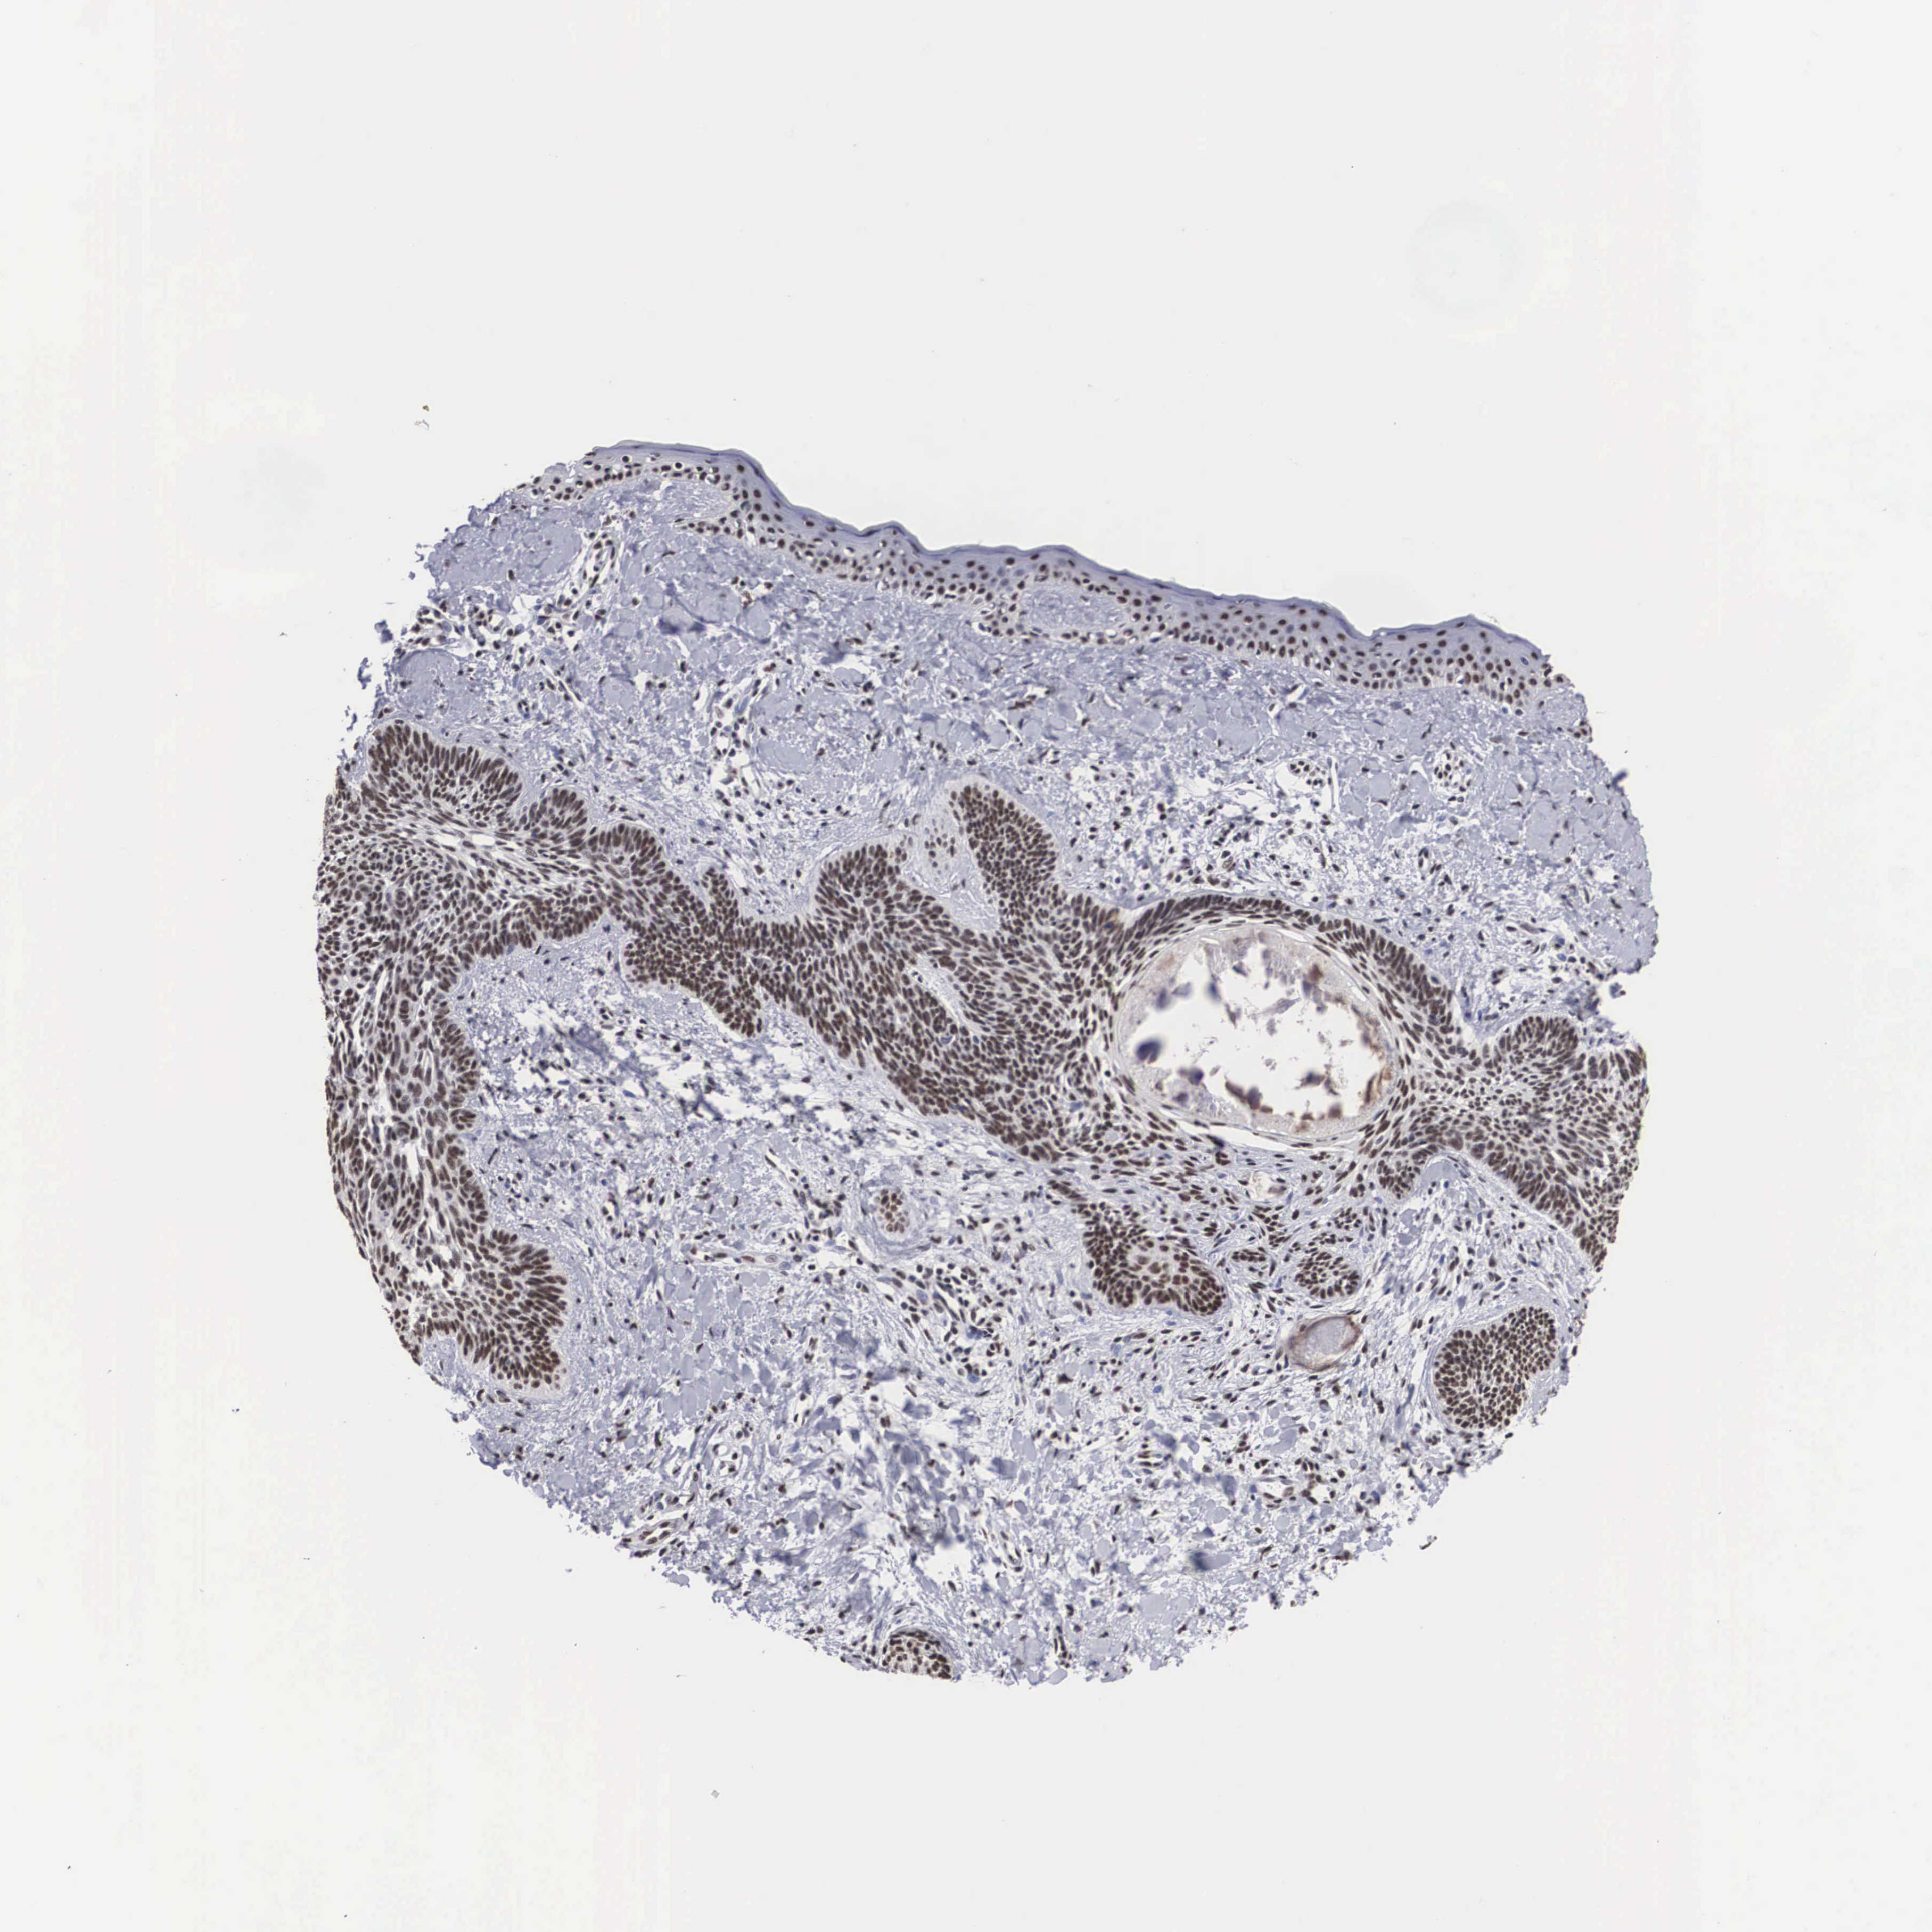

SKIN CANCER - Protein expressioni

A mouse-over function shows sample information and annotation data. Click on an image to view it in a full screen mode. Samples can be filtered based on level of antibody staining by selecting one or several of the following categories: high, medium, low and not detected. The assay and annotation is described here.

Each image is clickable and will lead to virtual microscopy that enables deeper exploration of all samples and also displays staining intensity scores, fraction scores and subcellular localization as well as patient and tissue information for each sample.

Antibody HPA000657

Staining

High

Intensity

Strong

Quantity

>75%

Location

Nuclear

Squamous cell carcinoma, NOS